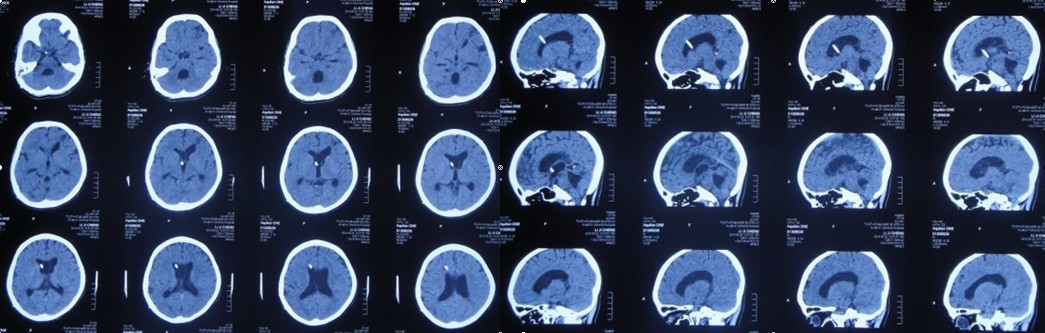

复查头CT:脑室系统较前无扩张